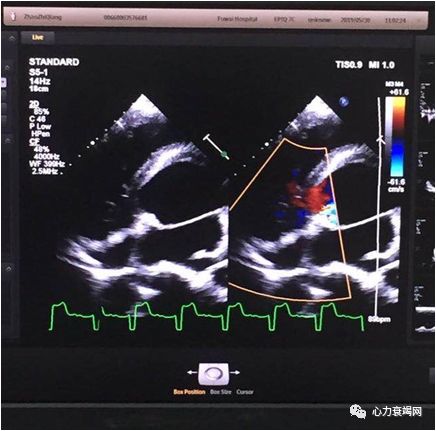

心脏彩超

主动脉瓣二瓣化畸形并前瓣叶脱垂,LV104,EF22%

主动脉瓣大量返流

肺动脉瓣中量返流

全心功能减退

肺动脉高压